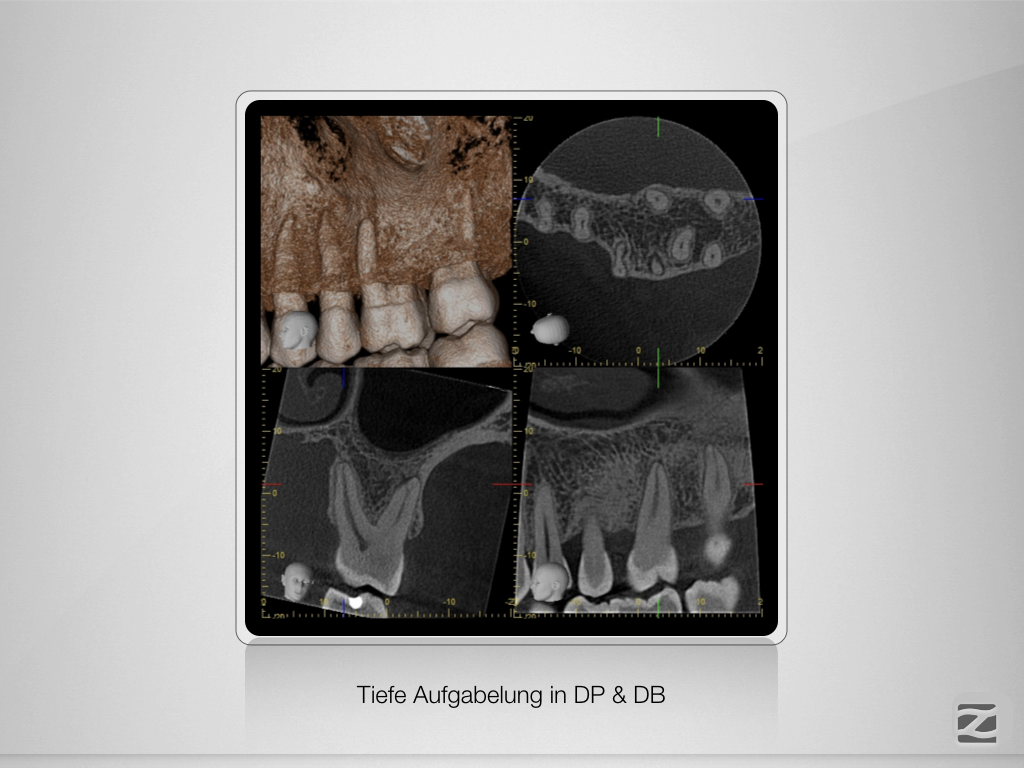

26D.006

Fluch und Segen!